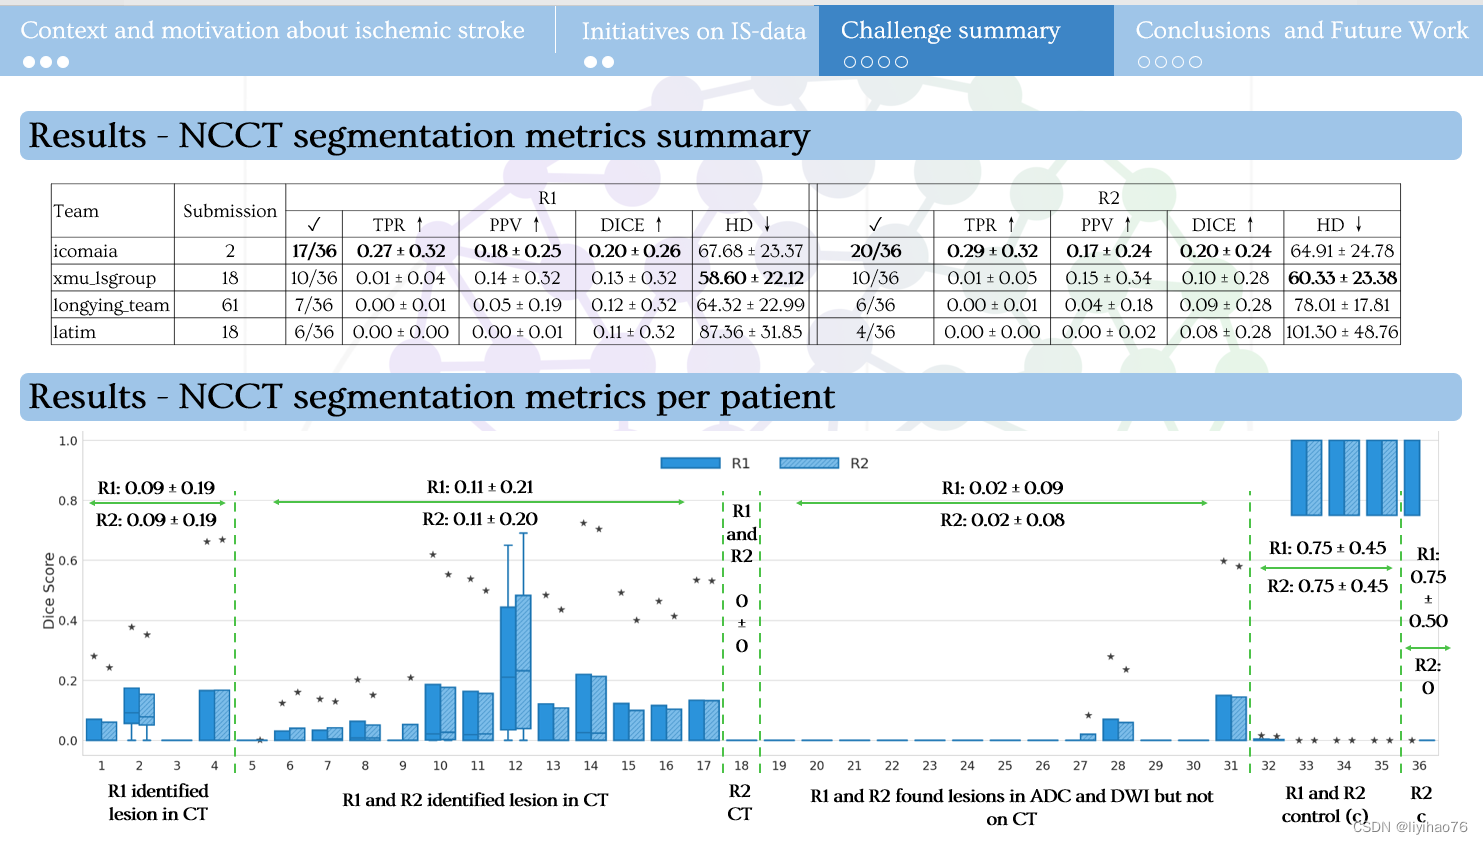

1.比赛任务及结果

5.比赛总结

- 由于病变的对比度差和低衰减,对缺血性中风 NCCT 序列的分割仍然具有挑战性。

- 目前在 ADC 序列上的工作可以以良好的性能分割病变,但在缺血病例的临床作用路径中是不可行的。

- 无论是模型、预处理还是其他方法都无法在 NCCT 序列上取得显着的结果。

- nnU-Net 在3D分割任务中依旧表现优异,数据预处理的不同可能会对分割表现有较大影响。